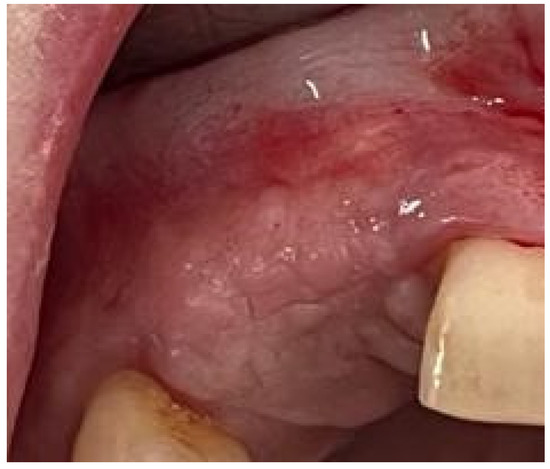

Background and Objectives: Alveolar ridge augmentation in the complex bone defect is a popular topic in implantology. Guided bone regeneration (GBR) is one of the most commonly applied methods to reconstruct alveolar bone. The application of a membrane is the fundamental principle of GBR. There are many membrane types used in oral surgery, but the advantage of the titanium mesh is the rigidity which provides space maintenance and prevents contour collapse. The smooth surface also reduces bacterial contamination. Using computer-aided design (CAD) and computer-aided manufacturing (CAM) in dentistry allows us to obtain the perfect architecture form of the mesh, which covers and protects the bone reconstruction. Case presentation: We present a surgical case of a 27-year-old female patient with severe aesthetic bone atrophy after a deficient odontectomy. Based on the GBR clinical applications, the technique consists of bone reconstruction and a customized titanium mesh application. Using mesh titanium in this case presentation was a reliable alternative to perform a lateral alveolar bone augmentation and reconstruct ridge deformities before reaching an ideal implant placement. Conclusions: According to our case report, the customized titanium mesh could be a valuable option for guided bone regeneration in aesthetic maxillary defects. Full article